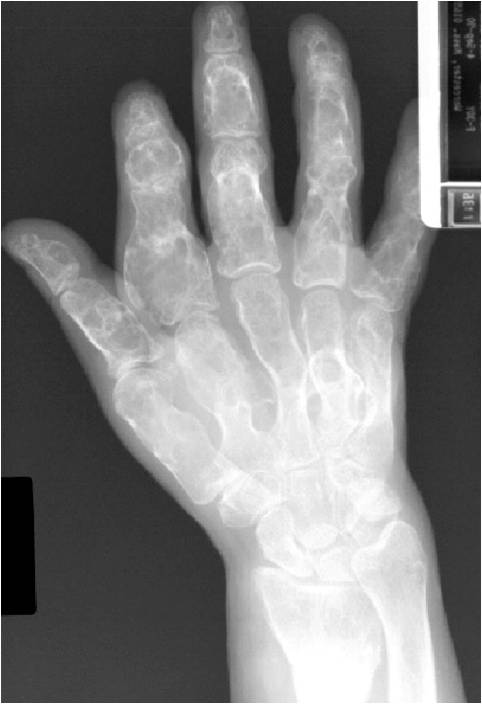

Geographic lesion Stippled calcifications in lesion Phalanx is expanded Significant endosteal scalloping No cortical destruction No soft tissue extension Cortex Scalloped and Expanded